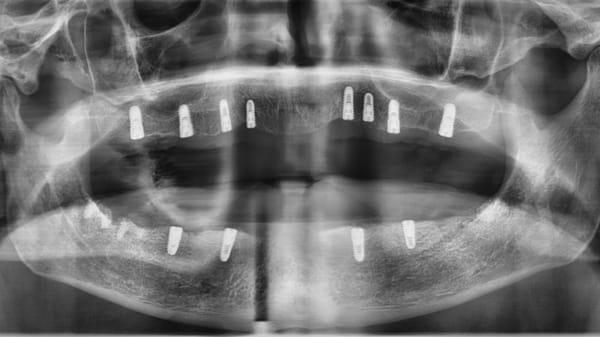

Centra Dental is a general dentist providing multiple services and treatments to families all throughout South Houston. We specialize in affordable Houston braces for children, teens, and adults, but we also offer other services including, but not limited to dental fillings, teeth cleanings, dental crowns and bridges, and root canals. We are very family-oriented, so we offer free Wi-Fi and family-friendly movies and games to keep visitors entertained while they wait for their appointments. In order to continuously provide the best, most comfortable care for our patients, we regularly learn about the latest dental technologies and methods by enrolling in extra hours of advanced education throughout the country. We then use our advanced background to proudly educate our patients so they can ensure their teeth are healthy when they leave our office. When it comes to compassionate and quality service, we proudly embrace your smile.